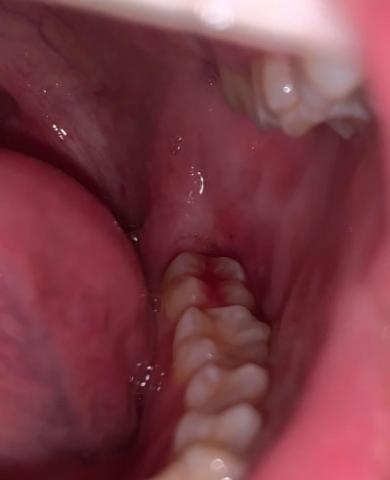

Focused Area: Posterior teeth (molar region) and surrounding gingival tissue

Localized gum redness and bleeding near the molar gum margin

Soft tissue appears inflamed and irritated

Area is difficult to clean, making it prone to plaque retention

No obvious fracture or large cavity visible at this zoom level

Possible early pocket formation cannot be ruled out without probing

Plaque-induced gingivitis in the molar region

Localized gingival trauma or inflammation

Early risk of posterior periodontal disease if untreated